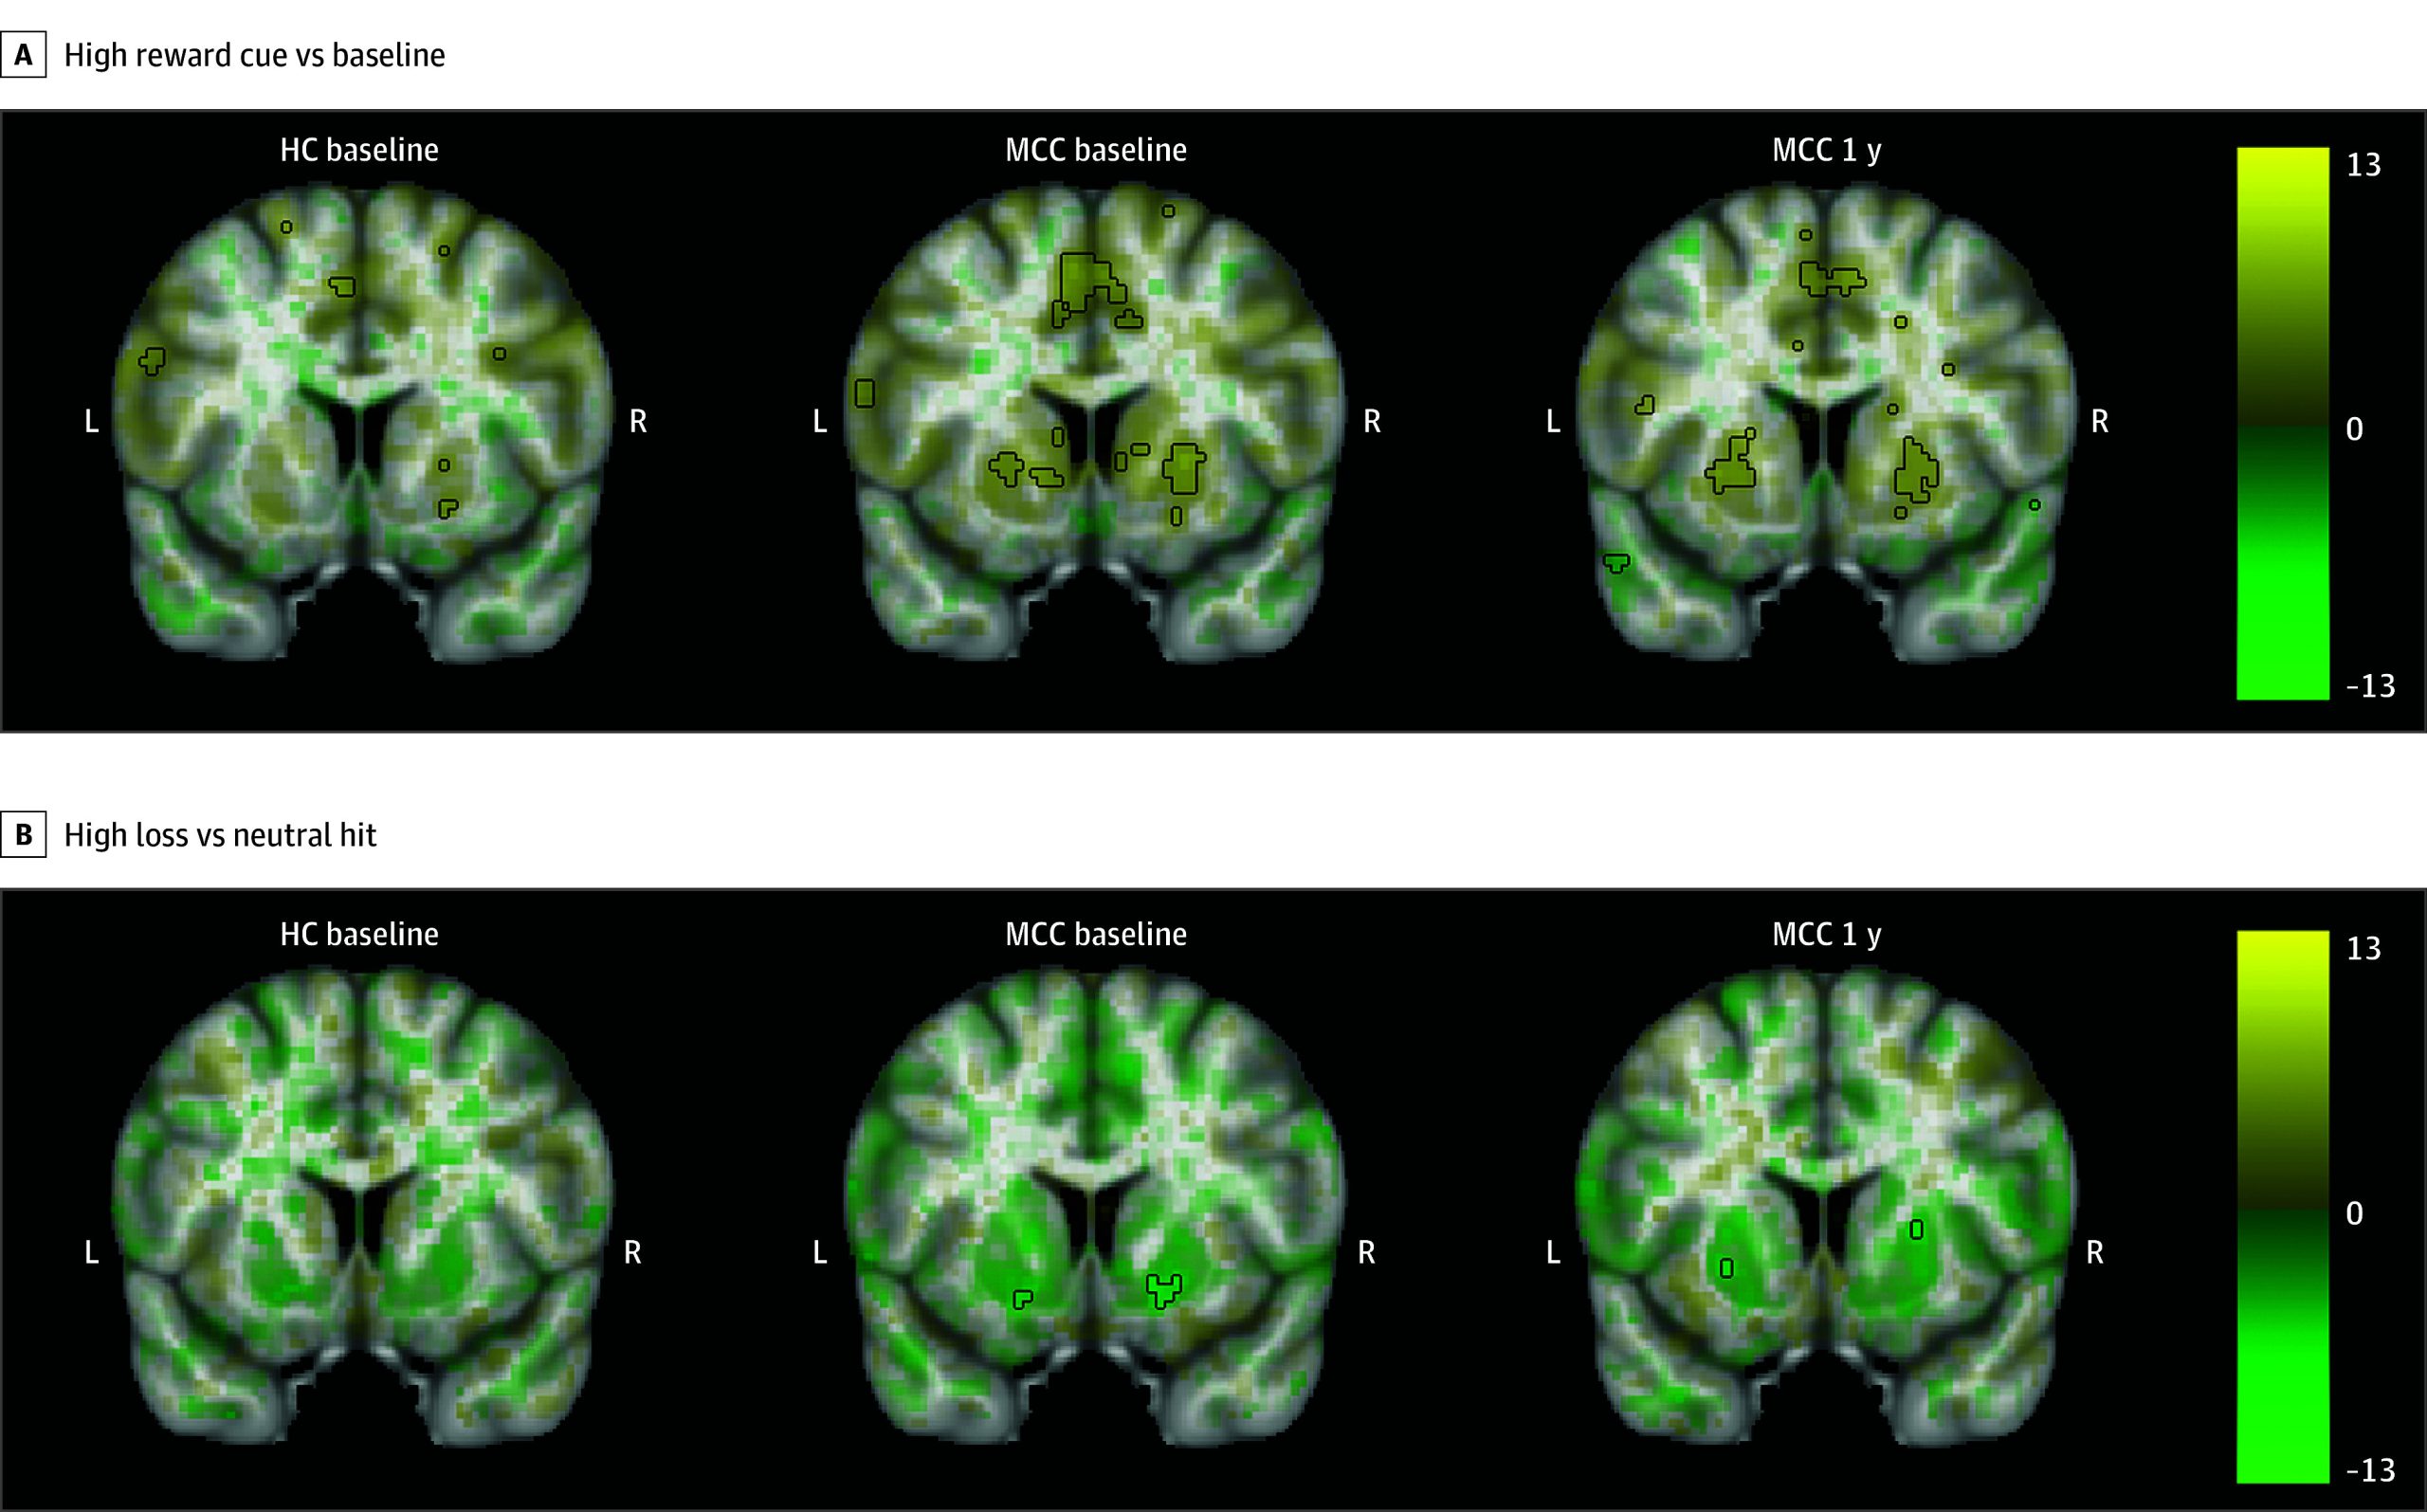

MCC participants at baseline and 1 year, as well as controls, showed activation in the bilateral basal ganglia during all cue contrasts, although activation only reached statistical significance during the high reward cue vs baseline contrast (Figure 2; eAppendix 1 and eFigures 6-8 in Supplement 1).30 During the reward vs missed reward feedback contrast, activation in the bilateral basal ganglia was observed, while during all other feedback contrasts, deactivation in the bilateral basal ganglia and insula was observed, although only significant in the high loss vs neutral hit contrast. No significant differences in activation were observed between the groups at baseline (23 HC participants and 35 MCC participants) or between the 2 time points of the MCC group (22 participants). Within the MCC group, there were no significant associations between brain activation at 1 year and cannabis use frequency changes.